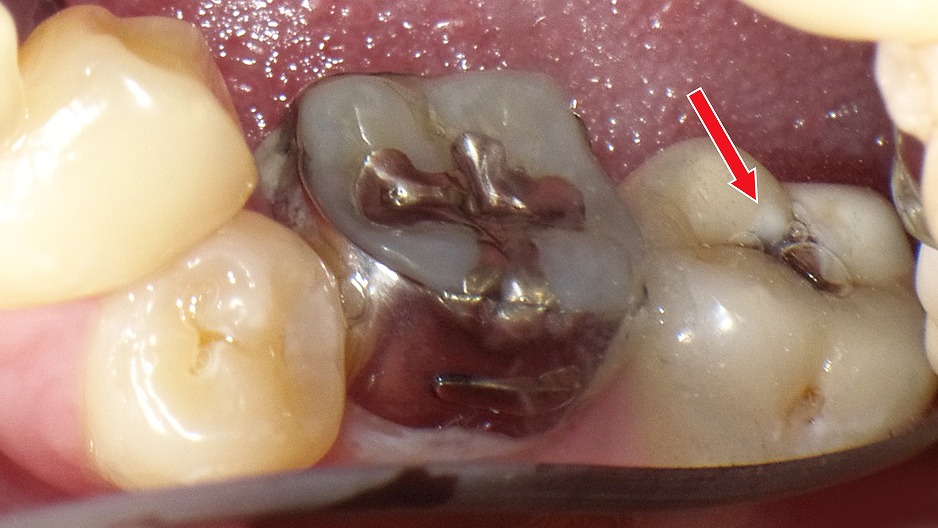

赤矢印が示すように、歯と歯の間(コンタクト部)の初期虫歯は、肉眼ではほとんど確認できません。レントゲンを撮影することで、エナメル質内部の透過像として虫歯を早期に発見できます。見た目に穴がなくても進行している場合があるため、定期的なレントゲン検査は非常に有効です。